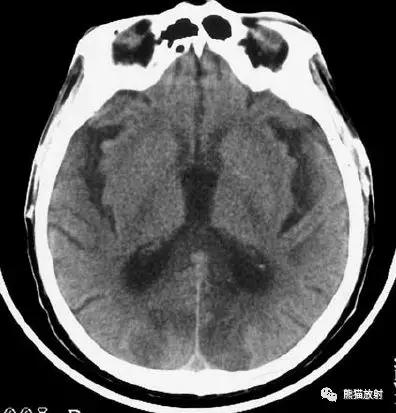

椎基底动脉区域的梗死:范围较广,非均质的低密度区域,累及脑干,小脑半球的前外侧以及颞叶的内后侧。